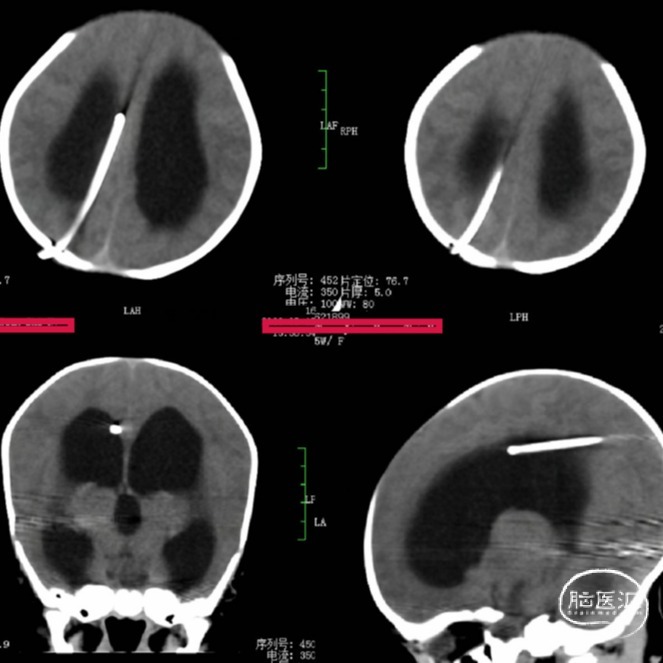

头颅CT(术后2天)

Evans index(EI)≈0.5